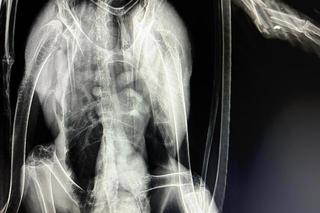

Na Podkarpaciu ktoś strzela do bocianów jak do żywych tarcz. W ostatnich dniach do Fundacji Ada w Przemyślu trafiło kilkanaście ptaków z ranami postrzałowymi. Jednego nie udało się uratować, był postrzelony aż 12 razy! Śrut zniszczył jego wątrobę, płuco, skrzydło i miednicę. Postrzelony bocian zazwyczaj kończy jako kaleki ptak, który już do końca życia nie będzie mógł żyć na wolności. Wszystkiemu winien jest człowiek.

Ostatnio fundacja zajmowała się trzema bocianami. Jednego z nich nie udało się uratować. Został postrzelony 12 razy.

- Ktoś sobie z tego bociana po prostu zrobił żywą tarczę. Miał w ciele mnóstwo śrutów, mnóstwo złamań. Niektóre były w okolicach płuc, serca - zaznacza lekarz weterynarii Angelika Szkolnik.